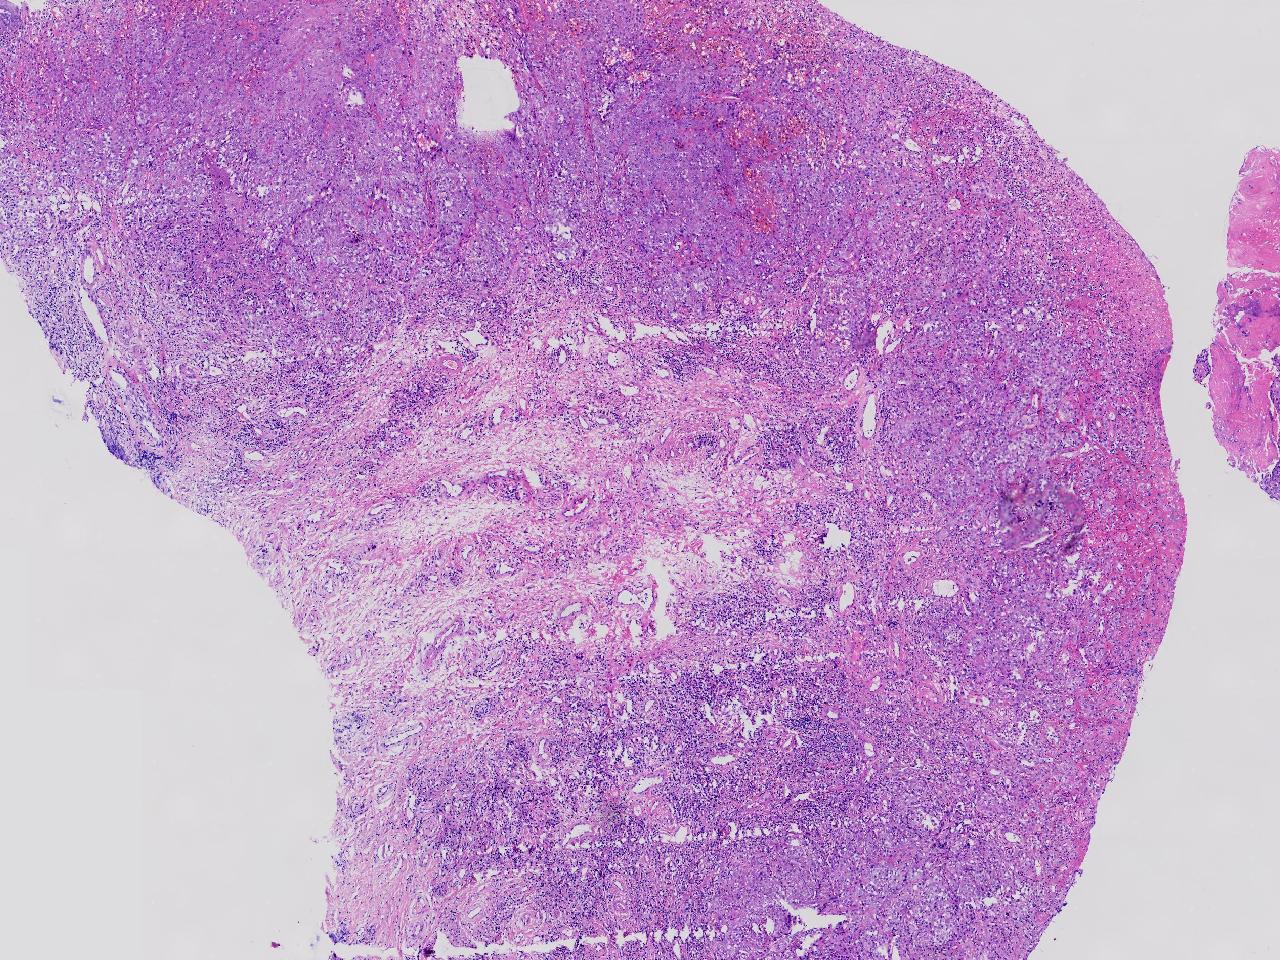

鳞癌?

性别

女

年龄

69岁

临床诊断

外阴肿物性质待查

一般病史

发现外阴肿物1月余,伴外阴疼痛,肿胀色素减退,表面分叶状。

标本名称

外阴肿物

大体所见

灰白色不整形软组织3块。

图2